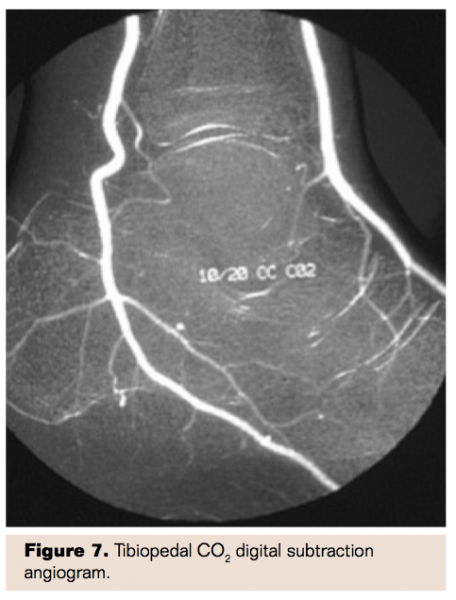

Carbon Dioxide Angiography

Without doubt the best way to avoid contrast nephropathy is simply not to administer any contrast. This has historically been possible using CO2 angiography13 but early systems were somewhat difficult to use, potentially dangerous to patients in the event of a mishap, and required use of large, bulky CO2 tanks. More recently, very portable, commercially available systems (Co2mmander, Portable Medical Devices) have been developed in which a very small canister of liquid carbon dioxide allows instantaneous conversion of liquid to gaseous CO2 that is easily administered using a double syringe system with a four-way stopcock (Figure 4). Many centers have adopted this system with highly satisfactory results and no patient safety issues. Angiographic images are of high quality for large vessels including aortoiliac studies as well as vessels as small as tibial and even pedal vessels (Figures 5-8). Placement of catheters as distally as possible in the circulation allows optimal imaging of smaller, distal vessels. Angiographic visualization has proven adequate for interventional procedures as well. The risk of contrast nephropathy is virtually zero, the cost of CO2 is extremely low, and there is no risk of contrast allergy further enhancing the safety profile of this approach.

Randomized studies have proven that there is no benefit to “benign” strategies such as the use of NAC and/or intravenous sodium bicarbonate. These approaches likely should be abandoned, just as use of intravenous fenoldopam was discontinued following the CONTRAST trial. Newer approaches such as the delivery of intrarenal fenoldopam using a specialized Benephit catheter should be considered although randomized trials are needed before this can be more widely adopted as standard of care. Finally, newer systems that facilitate the simple use of CO2 angiography should be utilized for peripheral procedures below the level of the diaphragm in patients at high risk of contrast nephropathy.